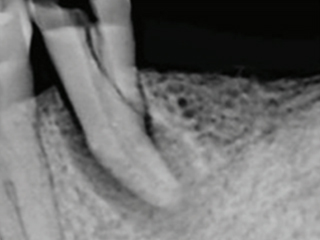

신경제거 후 신경으로부터 받던 영양분을 공급받지 못해 약해진 치아는 작은 충격에도 금이 가거나, 부러지거나, 깨져버리기 때문에 단단한 크라운을 씌워 치아를 보호해야 합니다.

신경치료를 위해 치아가 아래ㆍ위 치아가 닿지 않게 조절을 하며 치아에 구멍을 뚫어 놓기 때문에

씌워야 기능을 수복할 수 있습니다.